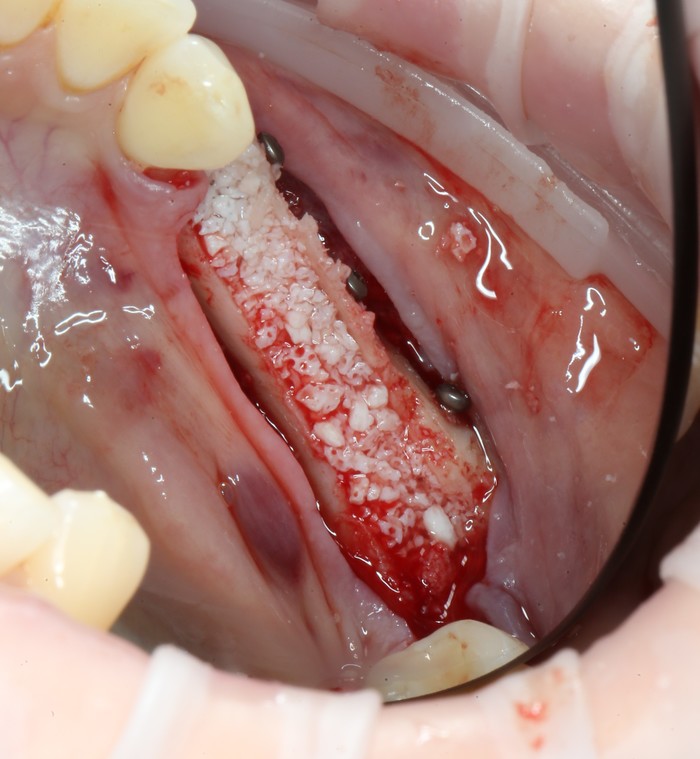

На верхней челюсти было дополнительно удалено два боковых резца с одномоментной установкой имплантатов, так же они были установлены в области четверок и шестых зубов. Дополнительно было проведено наращивание костной ткани - двусторонний синус - лифтинг. О том, что это такое, можно почитать ТУТ и ТУТ.